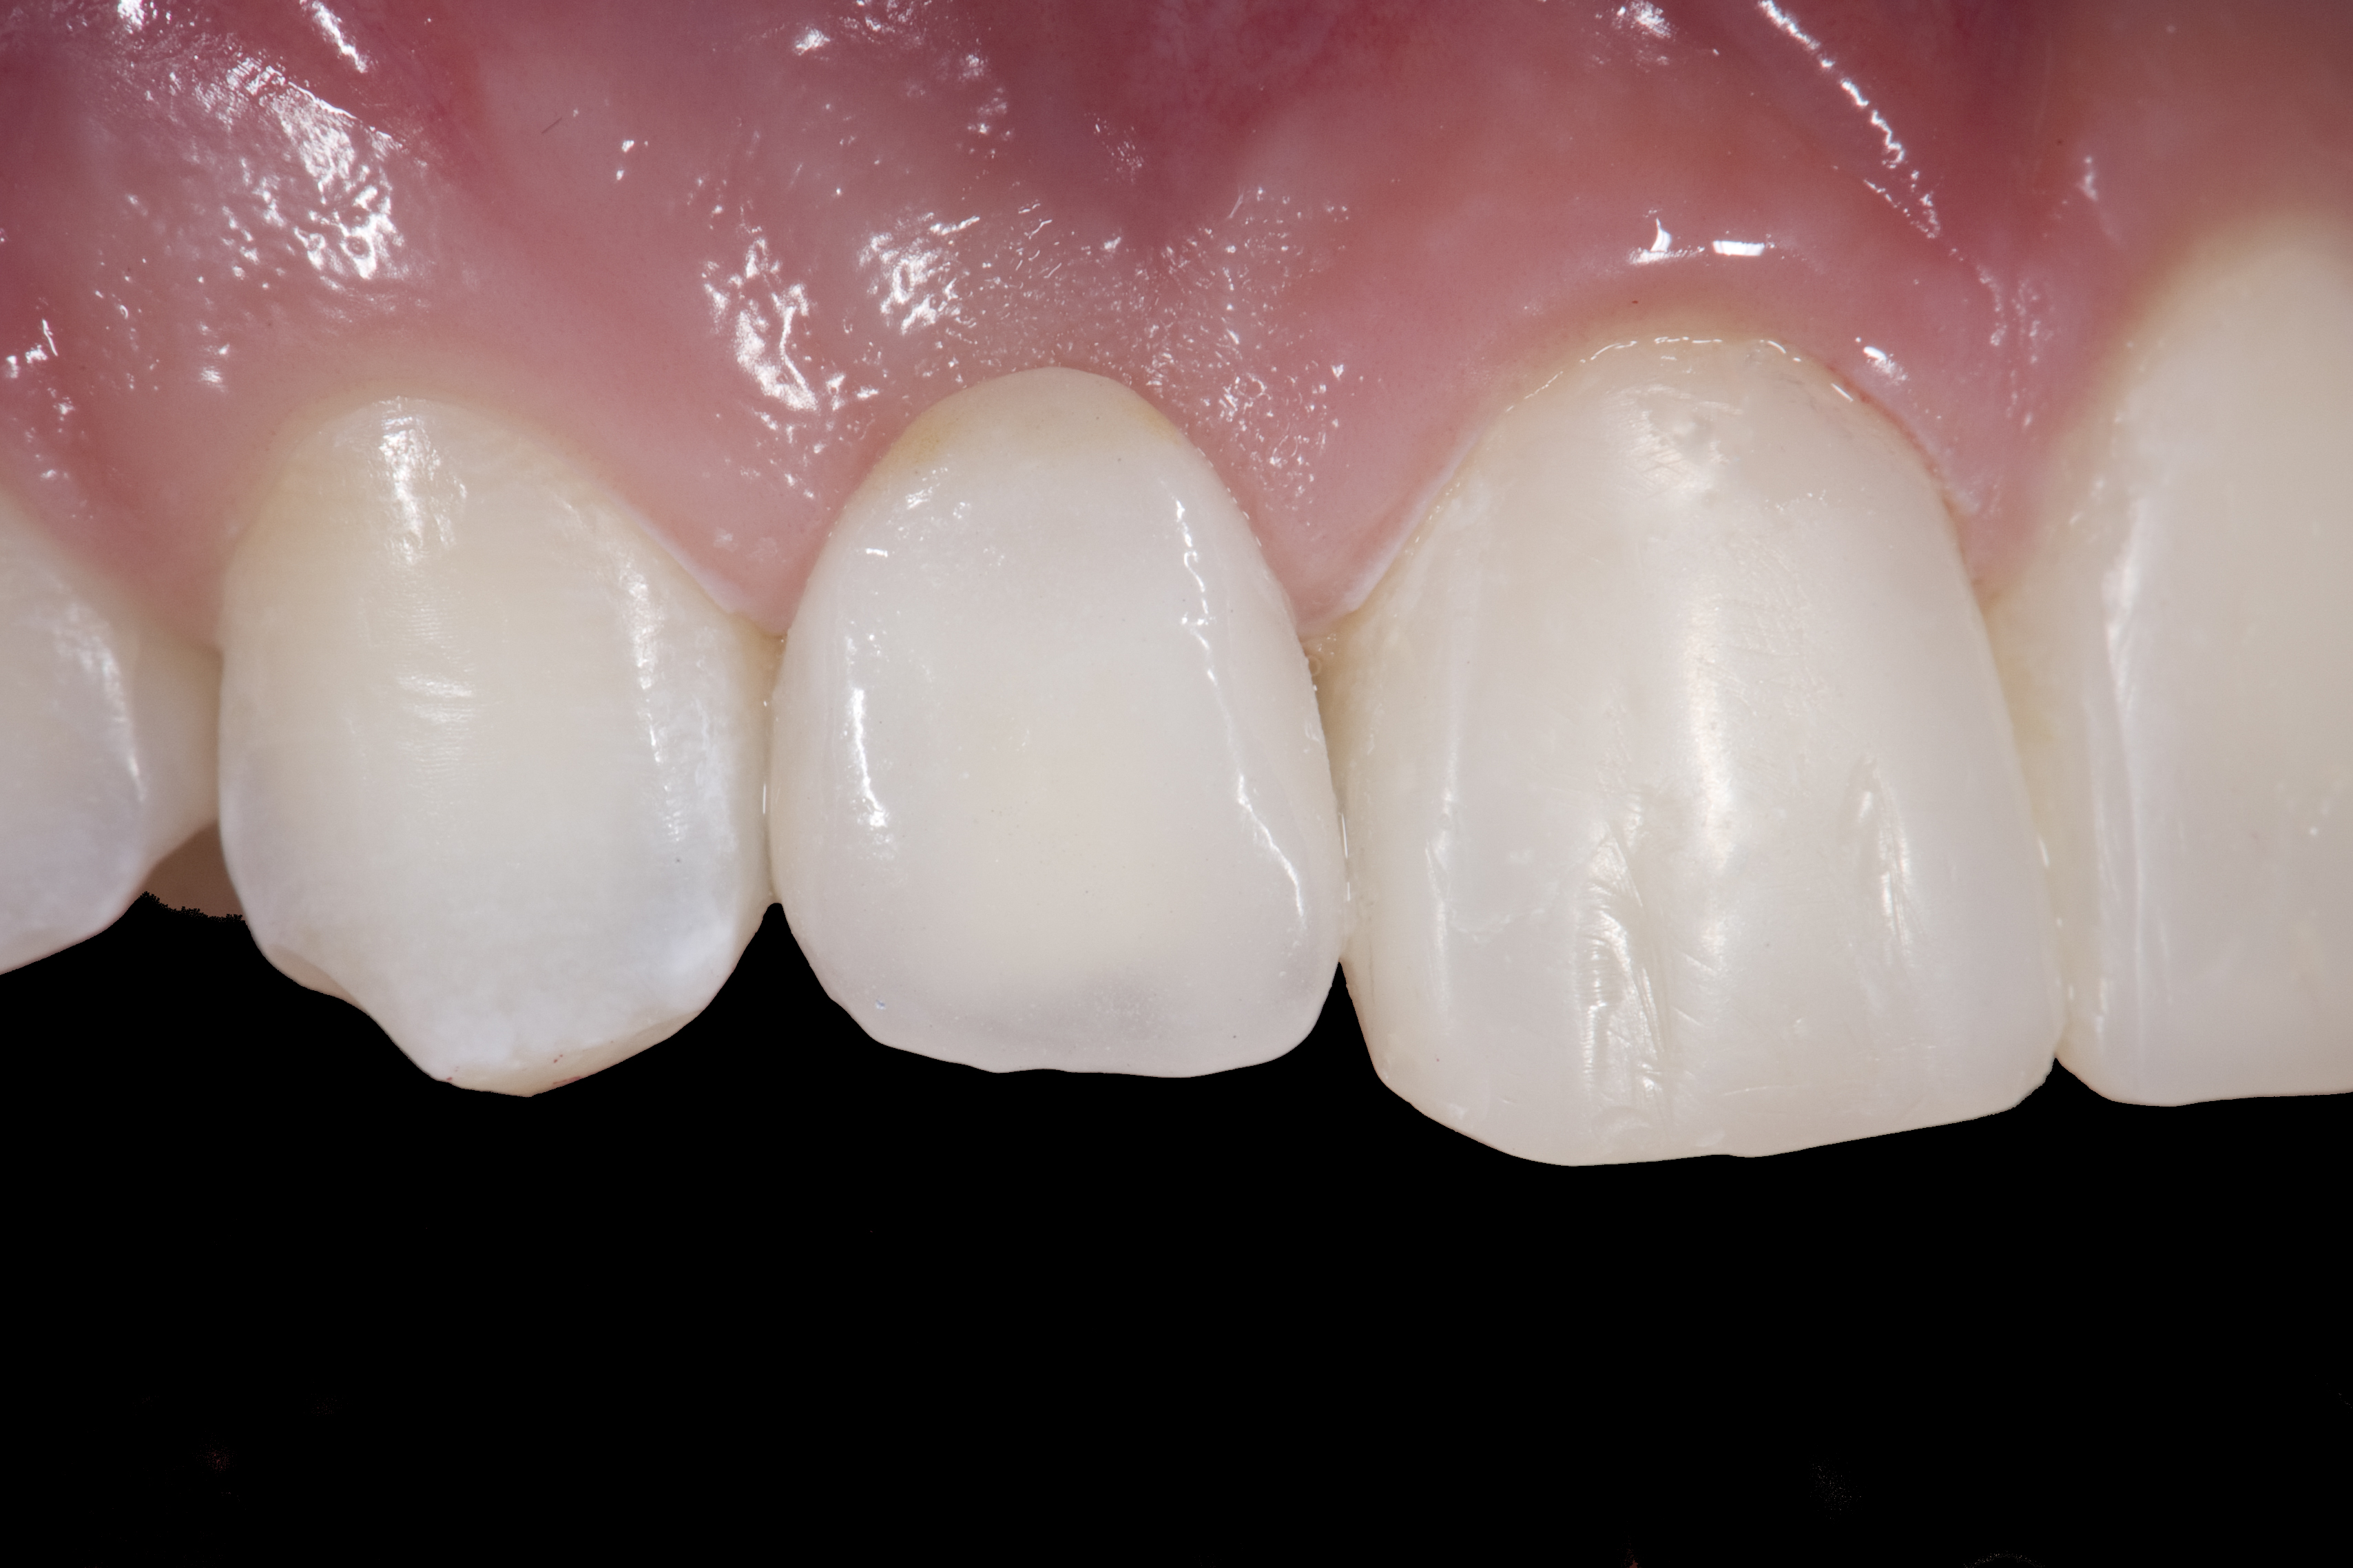

(13.) Deficient ridges in the areas of the missing lateral incisors.

Figure 13

Some patients do not want an implant due to the need for surgical intervention, and others may not have enough space for implant placement. A 15-year-old patient presented to the office after completion of orthodontic treatment to idealize the spacing of her teeth and improve her occlusal relationship (Figure 12 through Figure 14). Because both of her maxillary lateral incisors were missing, the patient was wearing a retainer with lateral incisor pontics. She had a busy school schedule, but expressed her desire for a fixed restorative option. All of her options were discussed, and the patient was informed that if she wanted an implant, she would have to wait for at least 3 to 4 years for completion of growth. The patient was not sure if or when she wanted to have an implant placed in the future, especially considering her busy schedule and desire to attend college after high school. Considering her age and the need to be conservative, a single-wing zirconia Maryland Bridge was chosen as the ideal prosthetic replacement option. Because bonding a non-etchable and smooth surface such as zirconia requires chemical adhesion, it was decided to use a modified technique to make the bridge more retentive. One of the ways to improve adhesion of a zirconia bridge is to use an etchable feldspathic ceramic layer on the internal surface of the zirconia retainer.56-58 Unfortunately, it can be difficult to determine the thickness of the ceramic and ensure accurate seating of the restoration.